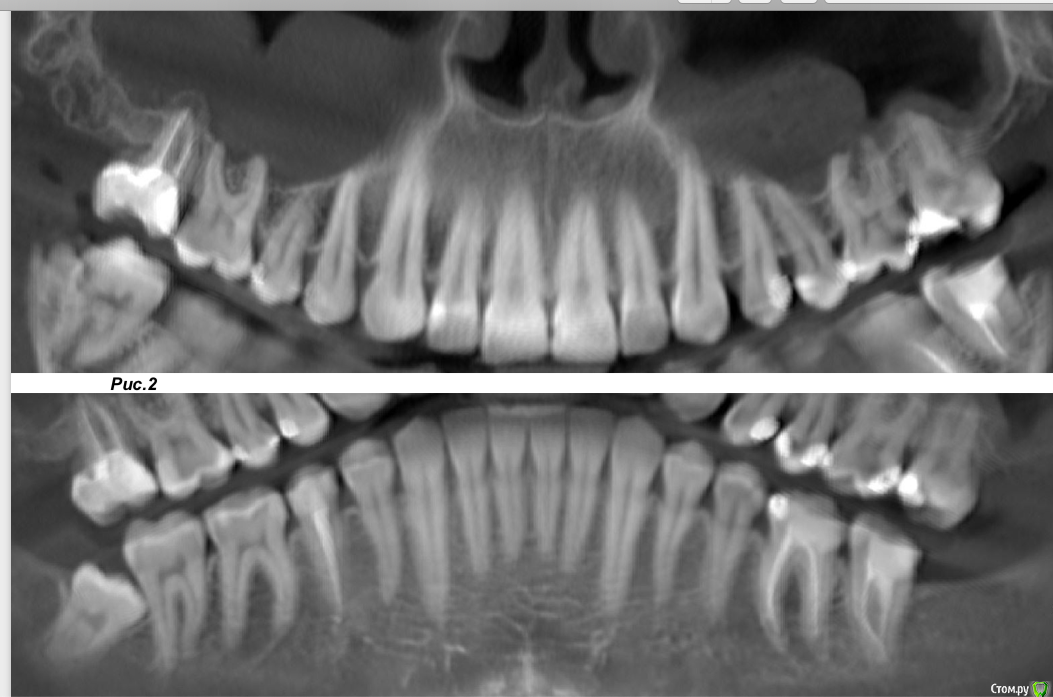

fly-away Опубликовано 12 февраля, 2020 Поделиться Опубликовано 12 февраля, 2020 (изменено) Подскажите пожалуйста, это можно лечить или нужно удалять?Фото в аттаче. 1.7 зуб(Рис.3) — депульпированКоронковая часть— пломбы на мезиально-окклюзионной и дистальной (с нависающим краем) поверхностях.Вариант строения — три корня / четыре канала. МЩ корень содержит два канала, открывающихся самостоятельными апикальными отверстиями (тип ІV).Степень и характер обтурации каналов: МЩ1 канал гомогенно заполнен пломбировочным материалом до рентгенологического апекса с выводом линейного фрагмента материала до 3.0 мм за пределы корневого канала через пространство очага деструкции костной ткани и кортикальную пластинку дна правого верхнечелюстного синуса в его утолщенную слизистую оболочку;МЩ2 канал гомогенно заполнен пломбировочным материалом до рентгенологического апекса с выводом линейного фрагмента материала до 3.0 мм за пределы корневого канала через пространство очага деструкции костной ткани в кортикальную пластинку дна правого верхнечелюстного синуса, и фрагмента материала до 1.5 мм за пределы корневого канала через пространство очага деструкции костной ткани и кортикальную пластинку дна правого верхнечелюстного синуса в его утолщенную слизистую оболочку; канал ДЩ корня гомогенно обтурирован пломбировочным материалом до рентгенологического апекса;канал небного корня гомогенно заполнен пломбировочным материалом до рентгенологического апекса с выводом линейного фрагмента материала до 5.3 мм за пределы корневого канала через кортикальную пластинку дна правого верхнечелюстного синуса в его утолщенную слизистую оболочку.Периодонт: в области апексов щечных корней определяется очаг деструкции костной ткани овальной формы, гетерогенной (содержит внутри фрагменты пломбиро 10.5х3.5х5.0 мм (ШхВхГ), истончающий, ремоделирующий и нарушающий целостность кортикальной пластинки дна правого верхнечелюстного синуса на участках до 0.8 мм; периодонтальное пространство вокруг небного корня не расширено.Пародонт: резорбция с дистальной стороны до 1.2 мм. Кортикальные замыкающие пластинки межальвеолярных гребней сохранены. Изменено 12 февраля, 2020 пользователем Bier Ссылка на комментарий

Bier Опубликовано 12 февраля, 2020 Поделиться Опубликовано 12 февраля, 2020 Здравствуйте, докторам вот эти описания рентгенологов ни к чему )) снимок лучше тысячи слов ) Если после снятия пломбы от зуба что-то останется, то можно лечить. 1 Ссылка на комментарий